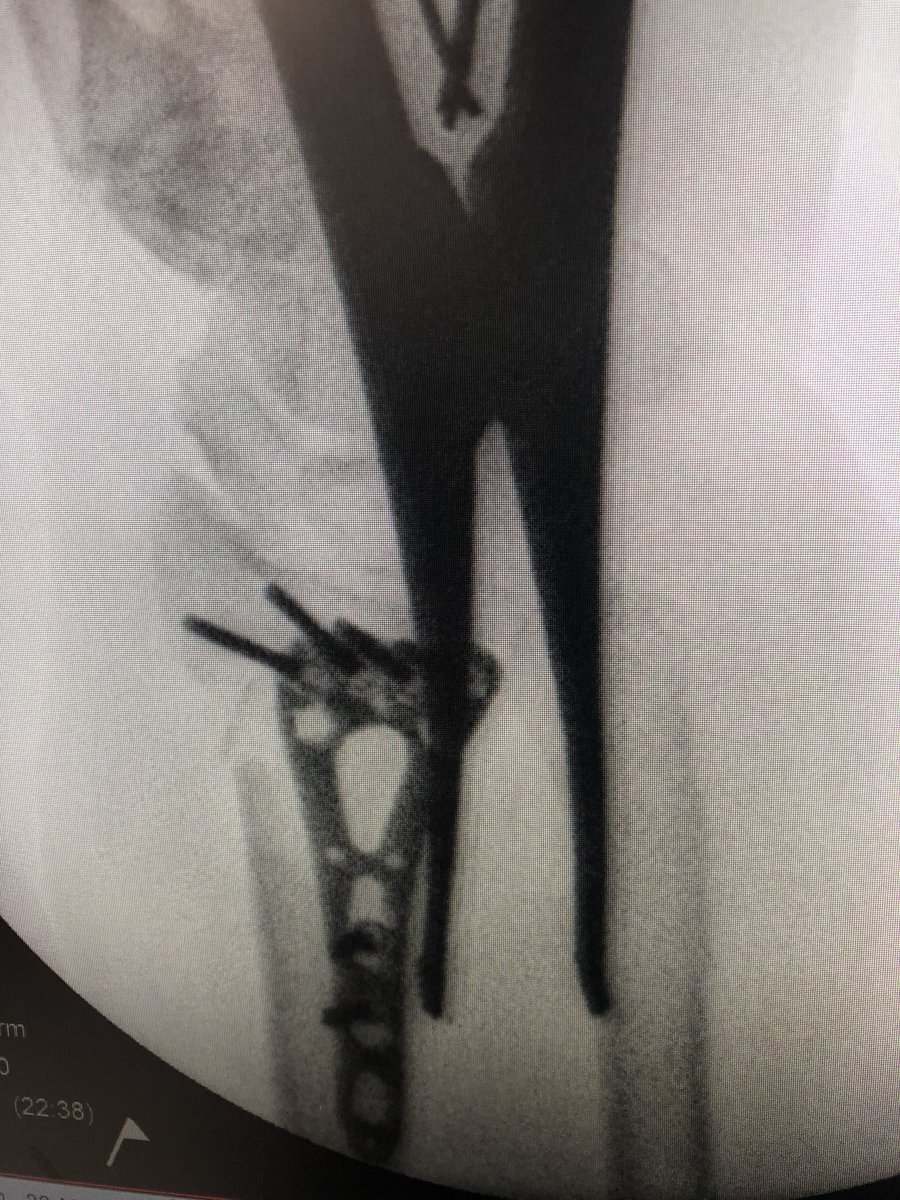

Before: the radial inclination is inadequately reduced. This shows itโ€™s impact on radial column, the DRUJ can be obstructed by the radius spike and the plate is โ€˜fish-tailingโ€™ proximal.